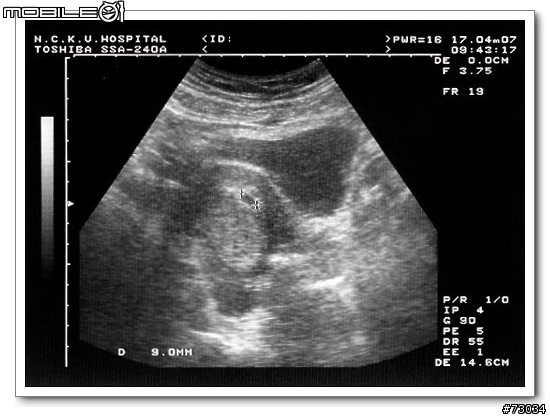

當這星期在超音波上看到僅有9mm如米粒般大小的胚胎時...

心中的感動是難以言喻的...

我想,妳也會跟我有同樣初為人父的喜悅~